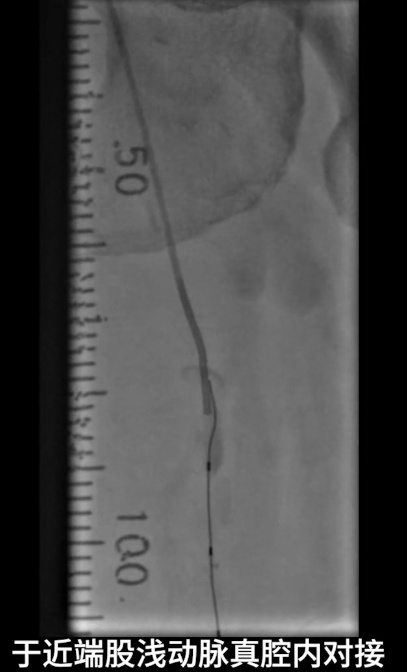

首先尝试顺行通过股浅动脉闭塞段,导丝进入内膜下,开通失败;遂改为逆穿策略,以支撑导管配合V18导丝逆行通过股浅动脉闭塞段,最终与近端股浅动脉真腔成功对接,建立安全操作轨道。